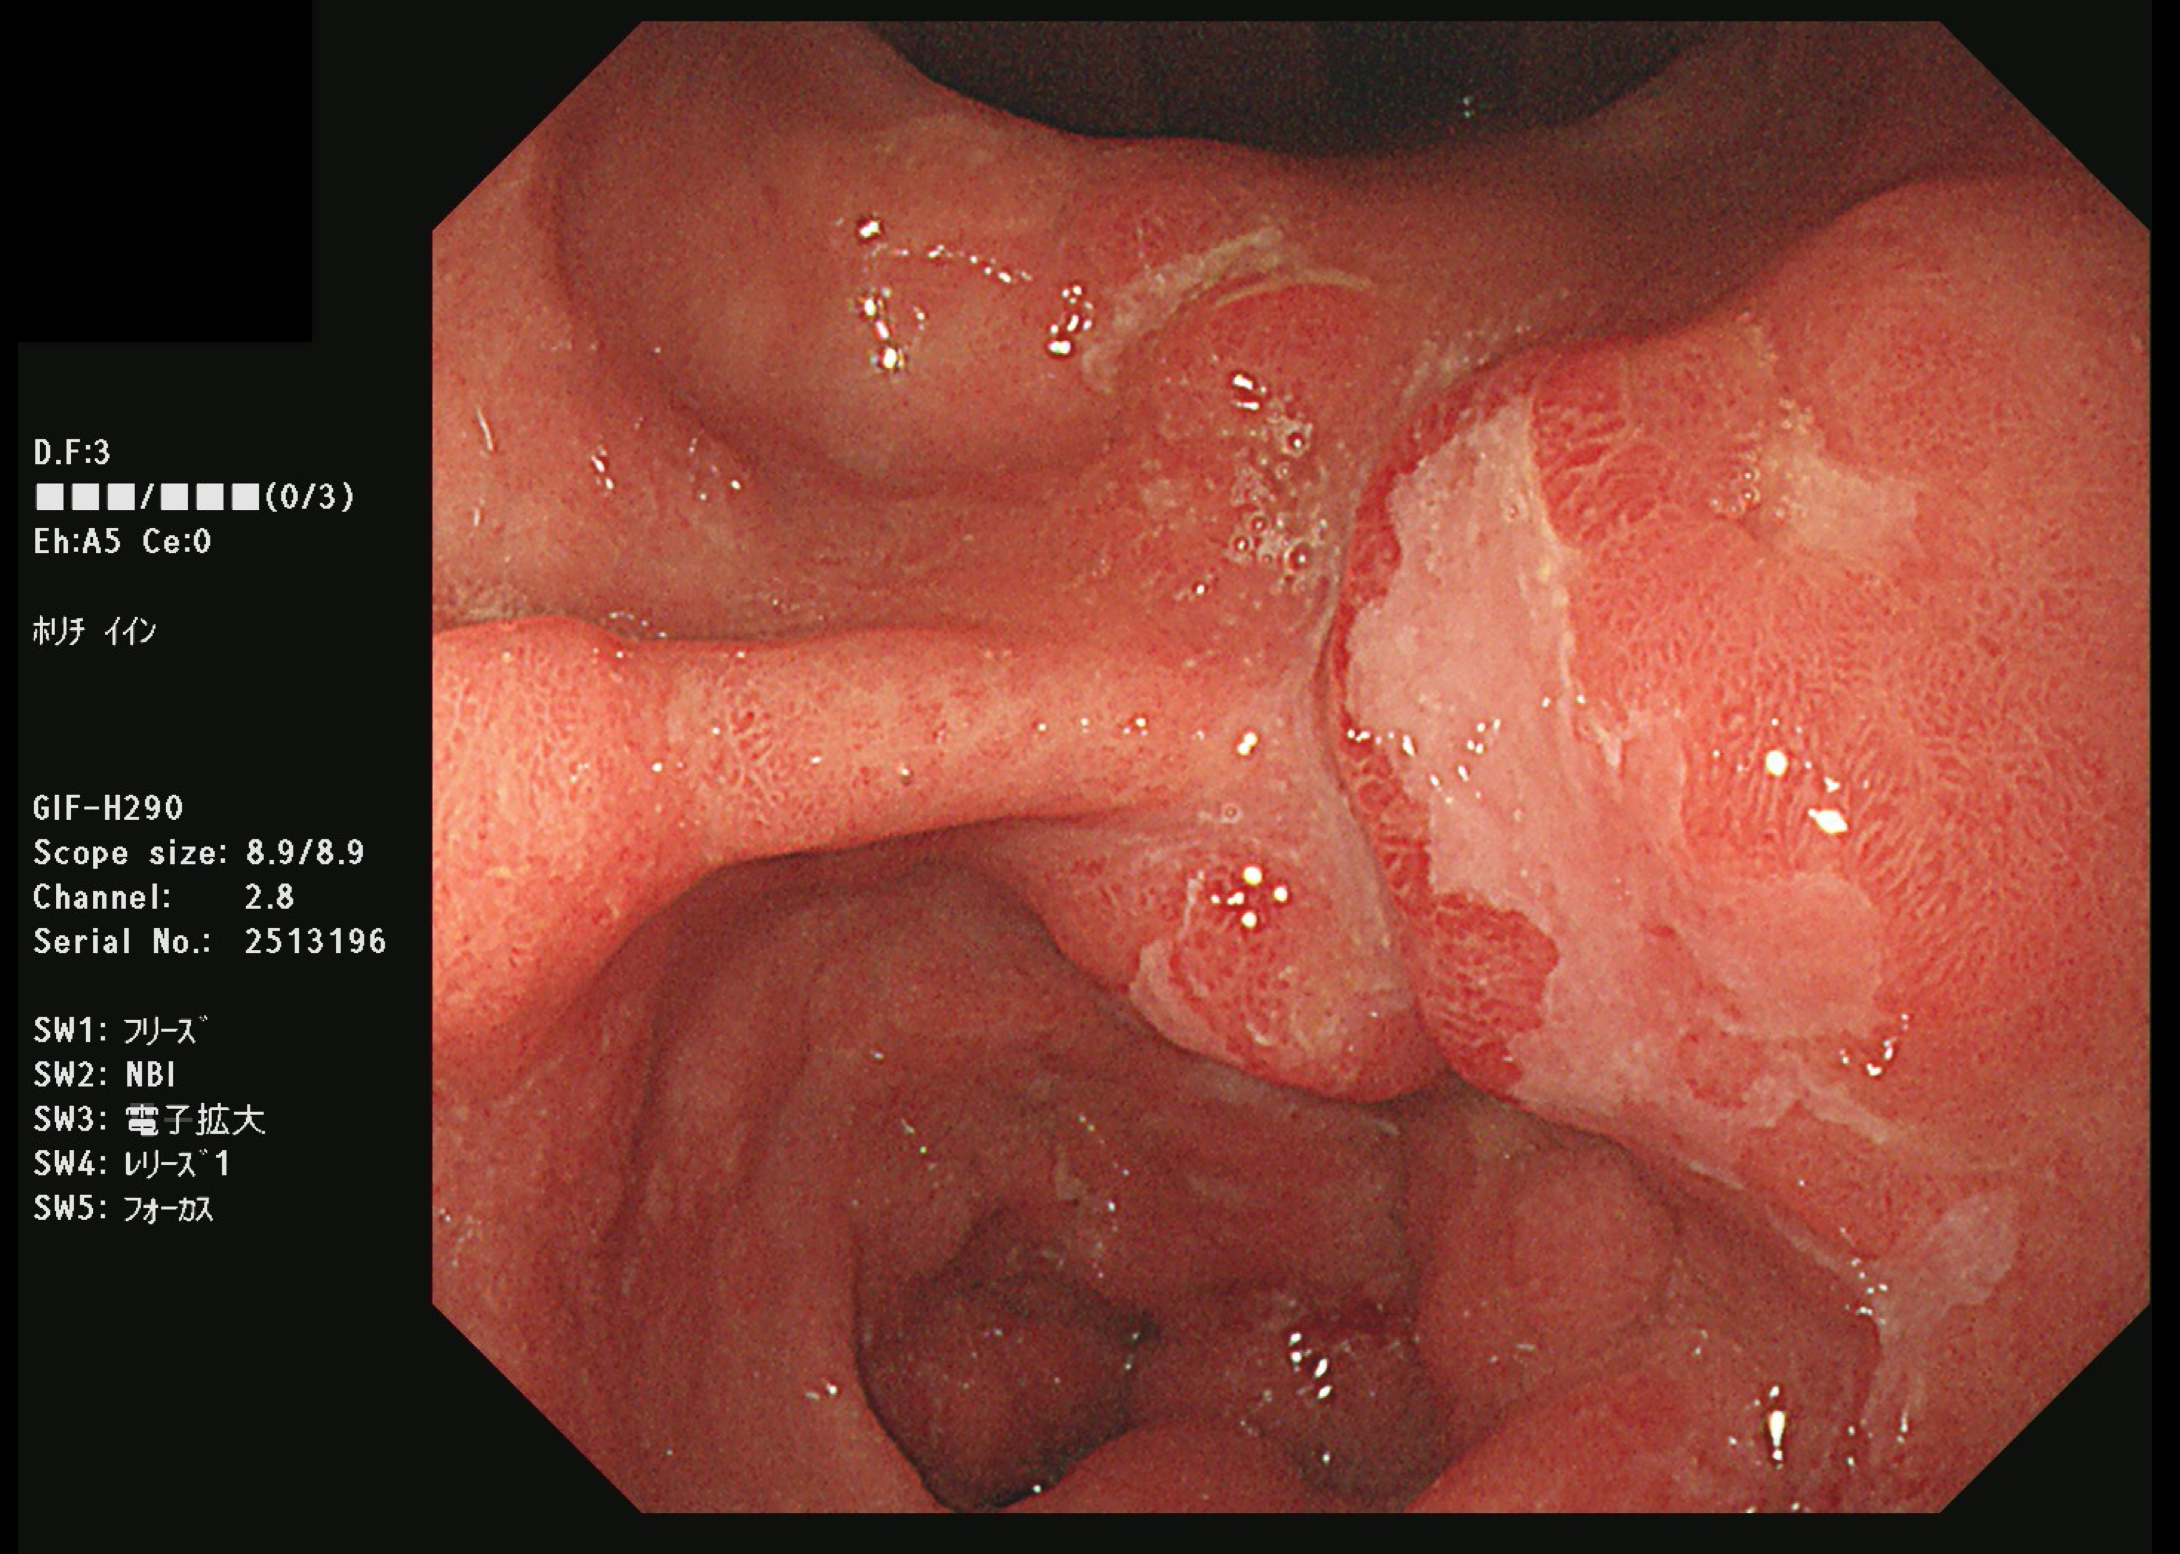

胃がん(上部消化管内視鏡)

胃がん検診

富山市の胃がん検診は胃内視鏡(上部消化管内視鏡)もしくは胃透視(バリウムを飲む検査)でおこなわれています。胃がんはかつては日本人にとって非常に多いがんでしたが、ヘリコバクターの保菌者の減少とともに、胃がんも少なくなりつつあります。

胃がん検診では喉頭部・食道・十二指腸上部を観察します。

当院では胃内視鏡(経口)のみを実施しております。胃の中を十分に検査するために高解像度の内視鏡を使用しており、そのため口からの内視鏡検査となります。一般的に鼻からの経鼻内視鏡による検査の方が楽な検査と言われていますが、内視鏡が細い分、最新型の経口高解像度内視鏡に比べて解像度が落ちます。